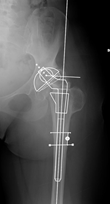

第一点,术前计划缺失,在我国非常常见,很少有骨科医生做图中这样的术前模板测量。但实际上术前模板测量在膝关节和髋关节中都非常重要,尤其是髋关节。髋关节的术前模板测量对于Offset重建尤为重要。因为我们在手术中间可以比较方便的恢复下肢长度,但很难完美重建偏心距。在国内,因为影像科条件、科室习惯、条件等原因,很少有人在术前进行测量。术中做股骨颈截骨时候非常随意,以恢复下肢长度为唯一目标,偏心距很难完美重建。

那么,怎么重建偏心距呢?首先术前要做好要模板的精确测量,确定截骨的位置、假体的型号;其次我们可以根据术中的模板进行比较,进行较为精确的股骨颈截骨;第三,可以在术中进行反复测试,测试软组织张力和下肢长短;第四,如果条件允许,选择合适的假体重构精确的Offset。我在加拿大西安大略大学医院关节中心进修的时候,Robert Bourn医生自己设计了一个测量尺,可以同时用于测量肢体长度和偏心距。我认为,我们只要可以做好术前测量,术中精确的股骨颈截骨,反复进行稳定性测试,就不一定需要这样的专门工具。